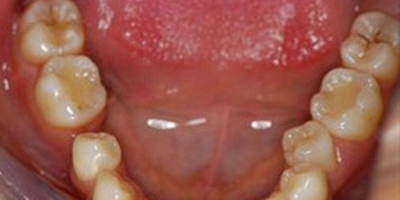

適宜人群 牙齒疼痛、牙齦出血、牙齦紅腫、牙周炎。

治療時間短,效果顯著,能有效緩解牙周炎。